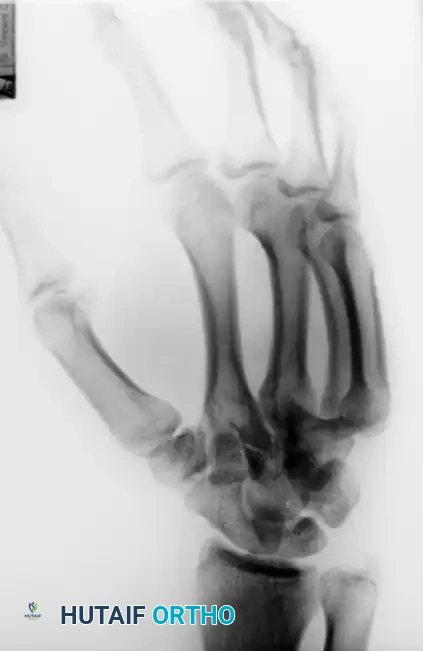

FIGURE 67-29 A-C: Preoperative radiographs of a small finger carpometacarpal fracture-subluxation in a 34-year-old man, demonstrating dorsal displacement and articular incongruity.

Surgical Technique for CRPP:

1. Perform closed reduction under fluoroscopic guidance.

2. Once anatomical alignment is confirmed, drive two 0.045-inch Kirschner wires (K-wires) percutaneously.

3. The wires are typically driven from the 5th metacarpal into the 4th metacarpal, and/or directly into the carpus (hamate) to provide rigid stabilization.

FIGURE 67-29 D-F: Postoperative radiographs showing the ring and small finger carpometacarpal joints reduced closed and stabilized with two 0.045-inch Kirschner wires.